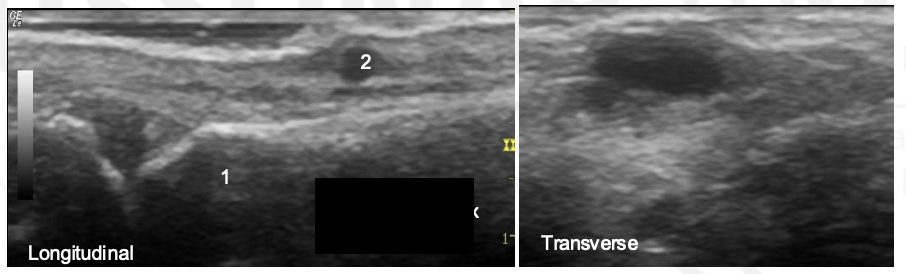

What is the arrow pointing to?

Synovial Distension

What is the abnormality?

1: Synovium, 2: Flexon Tendon, 3: Proximal Phalanx, 4: Middle Phalanx